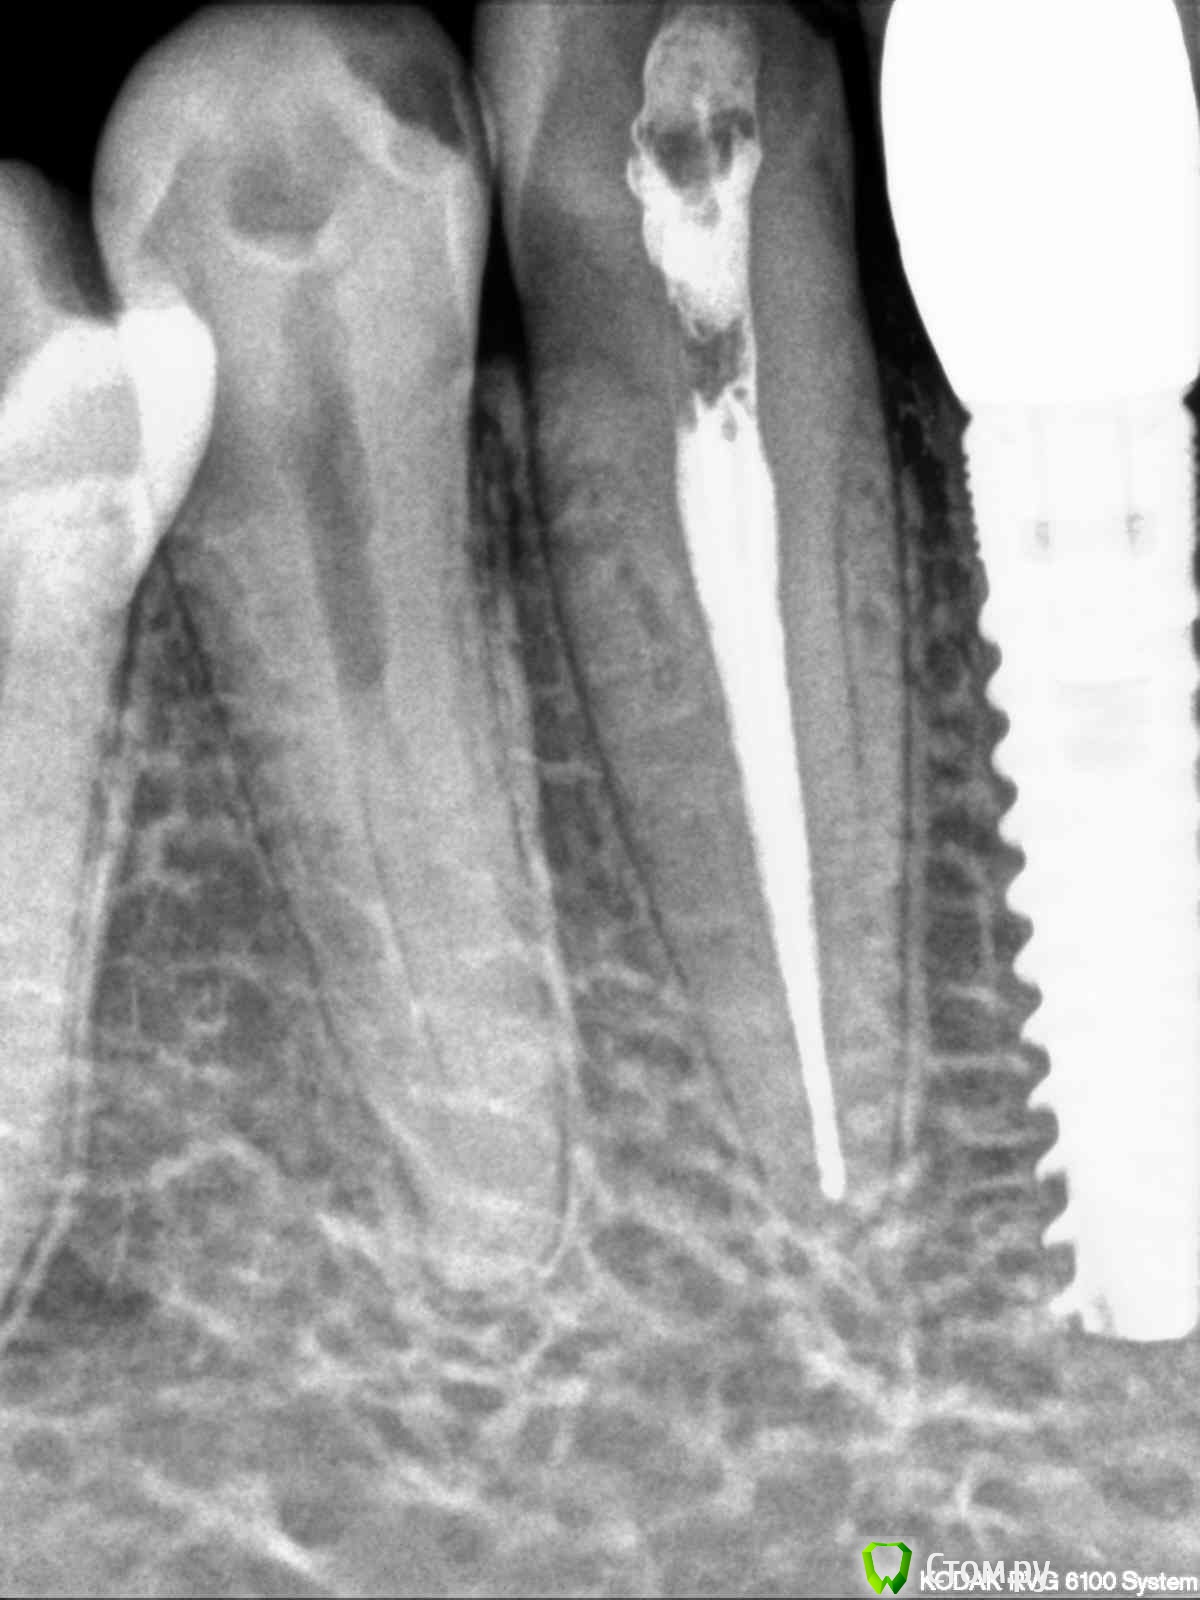

1) на 27 зубе периодонтит и эндодонтическое лечение неудачно.

3) на 43 зубе не совсем удачно вылечен канал

27 зуб вылечен конечно не очень, но пока рано судить жилец он или нет!!!!!вот 43 конечно надо перелечивать!!!!имплант 36 зуба, как то в самом деле в не очень хорошей ситуации!!!! А вот как прилегает коронка 47 и на что фиксированны коронки на имплантах по снимку к сожелению не определить!!!!

Уважаемые врачи, я сделала прицельные снимки 27 и 43 зубов. Если несложно, оцените пломбировку каналов. Не знаю какие снимки боллее удачные, поэтому разместила по 2 снимка каждого зуба. На 43 зуб надо ставить пломбу или коронки? Мнения в разных клиниках разошлись. Заранее спасибо за ответ.

post-36178-0-32966600-1385561030_thumb.jpg

post-36178-0-95622200-1385561042_thumb.jpg

post-36178-0-56636700-1385561054_thumb.jpg

post-36178-0-84859900-1385561065_thumb.jpg